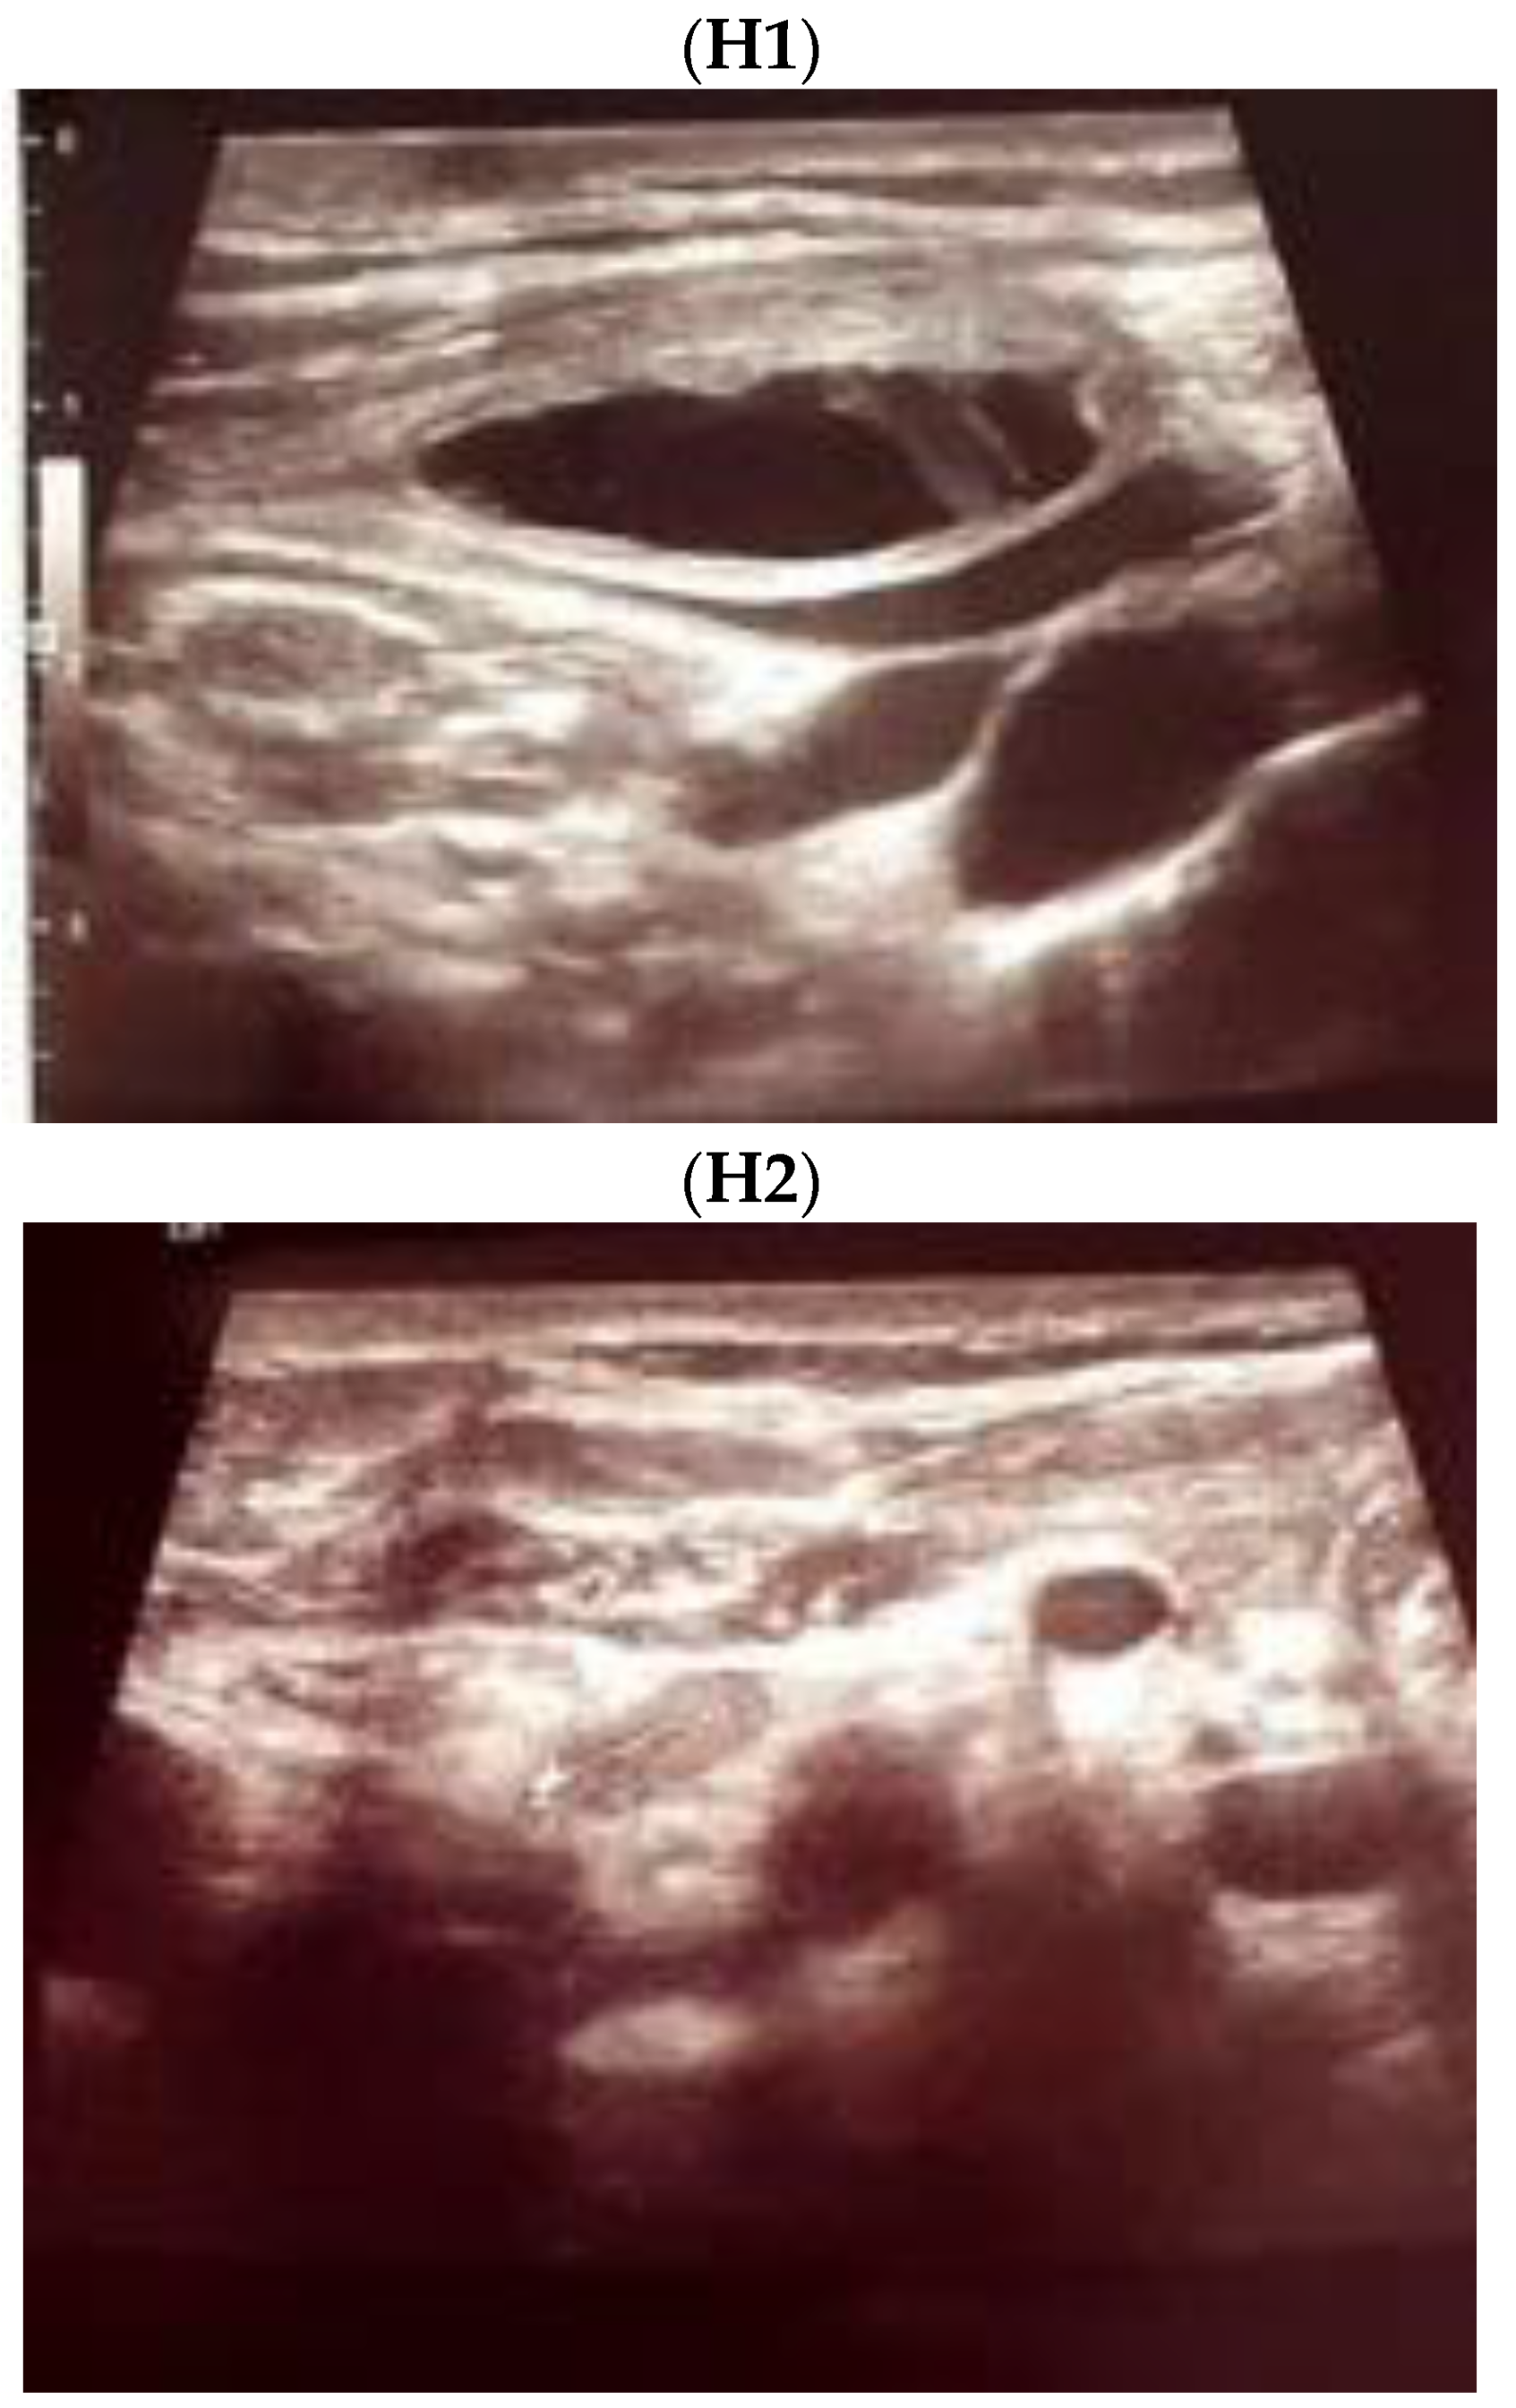

Ultrasound—guided fine need aspiration of the right mass provided cvasi-complete reduction of the liquid with stationary ultrasound features after 90 min. The liquid examination showed mature lymphocytes, rare erythrocytes, rare cholesterol crystals, lymph fluid, consistent with the diagnostic of lymphocele. A mild clinical improvement of HS—associated features was registered, but within 2 days, the neck mass rapidly regrew, and the patient was re-admitted. Under local anesthesia, there was a liquid evacuation (macroscopic aspect with milky-like aspect, a volume of 5–6 mL) and a drain tube was placed for 4 days. Ultrasound aspects showed a progressive regression of the right cystic mass with improvement of HS which slowly remitted within the next 2–3 months. (Figure 4).

Figure 4.

The evolution of within following weeks after thyroid surgery ultrasound features. (A). Right neck ultrasound aspect at the moment of fine needle aspiration (5 weeks since surgery)—on the right and 6 days after fine needle aspiration procedure (after cvasi-complete evacuation, the cystic mass relapsed within 48 h)—on the left. (B). Right neck ultrasound within the first day of tube drainage (6 weeks since initial surgery) showing a massive reduction of the cystic mass. (C). Drainage tube was removed after 4 days. Post-thyroidectomy scar and post-tube removal aspect. (D). Right neck ultrasound after 2 weeks from removing the drainage—persistent cystic mass, but with progressive improvement of HS (approximately 9 weeks since initial surgery). (E). Right neck ultrasound after another 2 weeks from removing the drainage –progressive reduction of cystic mass, but with remarkable improvement of HS (approximately 11 weeks since initial surgery). (F). Scar aspect 12 weeks since surgery and 5 weeks since lymphocele drainage. (G). Recovery of HS—approximately 8 weeks since drainage. (H1,H2). Bilateral neck ultrasound 20 weeks since thyroid surgery showing regression of the lesions on both sides versus prior examinations. (H1). Right later-cervical cystic collection of 2 by 2.8 by 0.9 cm (2.5 mL) and peripheral areas of fibrotic reorganization. (H2). Left later-cervical hypoechoic, inhomogeneous mass (no vascular signal) showing fibrotic reorganization (0.25 mL).